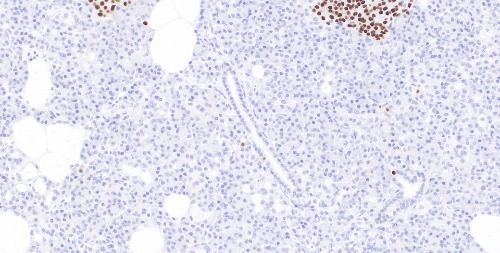

Immunohistochemical staining of human pancreatic tissue sections using INSM1 Rabbit Monoclonal Antibody (ARB848).

Immunohistochemical staining of human small cell neuroendocrine carcinoma tissue sections using INSM1 Rabbit Monoclonal Antibody (ARB848).